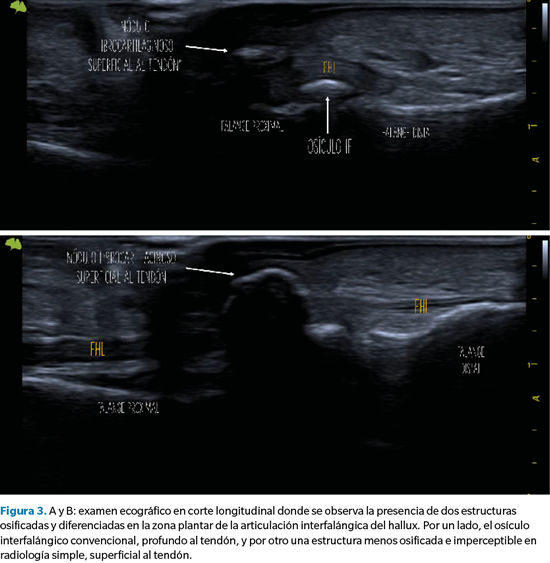

No obstante, para complementar el estudio se realizó un examen ecográfico en cortes, tanto longitudinal como transverso, mediante sonda lineal 14 Mhz con ecógrafo Vinno E35 (Vinno Spain, Vinno Ultrasound S.L.U., Barcelona, España). El estudio mediante ecografía se ha mostrado muy útil en estos casos, ya que permite identificar con mayor precisión estructuras tanto osificadas como no osificadas6.

En este caso, el examen ecográfico reveló información adicional muy trascendente de cara a la planificación quirúrgica y modificando el diagnóstico previo al observarse, además del osículo articular previamente identificado, una estructura ósea superficial al tendón flexor que muy probablemente era responsable de la sintomatología que presentaba la paciente. En base a este hallazgo, decidimos realizar una exéresis quirúrgica de esta estructura, pero respetando el osículo articular y preservando en todo momento el tendón (Figura 3).